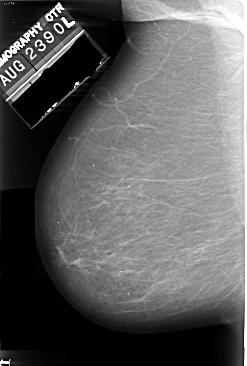

A_1005_1.LEFT_CC

LEFT_CC LINES 5476 PIXELS_PER_LINE 3376 BITS_PER_PIXEL 16 RESOLUTION 42 NON_OVERLAY

FILE: A_1005_1.RIGHT_CC.OVERLAY

TOTAL_ABNORMALITIES 1

ABNORMALITY 1

LESION_TYPE CALCIFICATION TYPE PUNCTATE DISTRIBUTION CLUSTERED

ASSESSMENT 4

SUBTLETY 2

PATHOLOGY MALIGNANT

TOTAL_OUTLINES 1

BOUNDARY